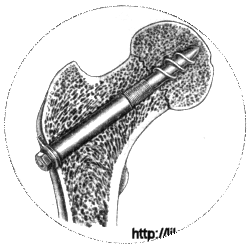

Для остеосинтеза чаще всего используют трехлопастный гвоздь Смит-Петерсена или его модификации. Трелопастный гвоздь обеспечивает стабильный остеосинтез. Линейным разрезом длиной 7-10 см по наружной поверхности бедра обнажают подвертельную область. У основания большого вертела долотом делают зарубки соответственно лопастям гвоздя; под постоянным телерентгенологическим контролем в двух проекциях вводят гвоздь. Он должен пройти по середине шейки бедра в центр головки до кортикального слоя. Исключение составляют субкапитальные переломы, при которых такой метод не обеспечивает надежной фиксации маленького проксимального отломка. Для лучшей фиксации фрагментов кости при субкапитально переломе гвоздь проводят через сустав и вбивают в дно вертлужной впадины так, чтобы конец его выстоял в полость таза на 1 - 1.5 см.

Если операцию проводят без постоянного телерентгенологического контроля, наибольшую сложность представляет выбор направления проведения гвоздя. Предложены различные аппараты - направители для введения трехлопастного гвоздя под периодическим рентгенологическим контролем в двух проекциях. Одним из наиболее простых методов остеосинтез является применение в качествен направляющей 2-3 толстых градуированных спиц. После рентгенографии выбирают наиболее правильно расположенную спиц и по ней вводят трехлопастный гвоздь.